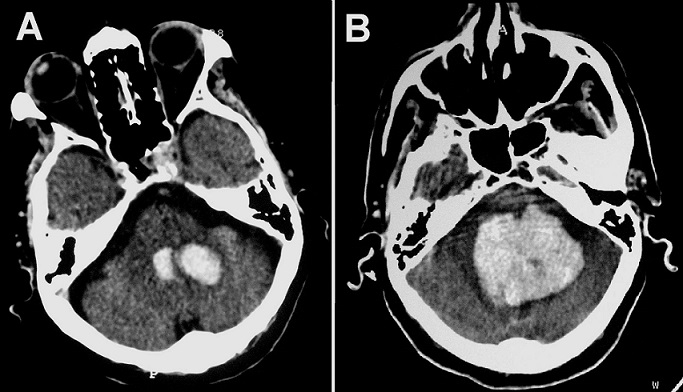

Intracerebral hemorrhage is one of the most devastating forms of stroke especially in the posterior fossa. Expansion of cerebral hematomas was common in the acute phase (< 6 hours) but rarely reported 24 hours later. A 70-year-old man, with history of hypertension, was admitted to the emergency service with the complaint of headache, dizziness and vomiting. He was neurologically intact except for neck stiffness. A cranial CT-scan demonstrated a left hemispheric cerebellar hematoma (about 2 cm in diameter) and a fourth ventricular hemorrhage without hydrocephalus (A). The patient was kept under observation. About 32 hours of onset, the patient complained of severe occipital headache and sudden loss of consciousness. He was brought to the ICU, where he appeared drowsy and bradipnoic. Neurological examination showed anisocoria. An emergency CT-scan revealed an increase of hematoma volume, the diameter was about three times as large with acute hydrocephalus (B). The patient was transferred to the operating room but unfortunately died before performing any surgery. This case shows that we should always consider the risk of hematomas enlargement or re-expansion following a hemorrhagic stroke. This secondary phenomenon can occur late and may be cause a rapid fatal outcome if not detected and managed early.